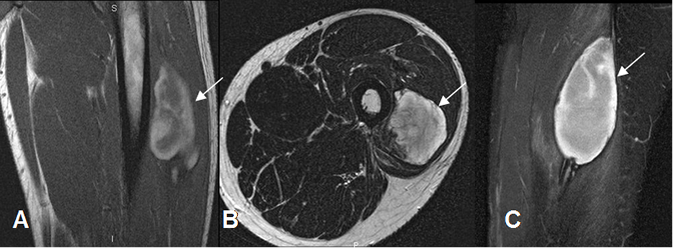

Fig 14 A. Hematoma muscular subagudo.

A: RM coronal en T1. Colección heterogénea, con áreas hiperintensas por evolución subaguda, en el músculo vasto externo.

B: RM axial en T2 y C: RM sagital en STIR. Colección intramuscular, definida e hiperintensa.